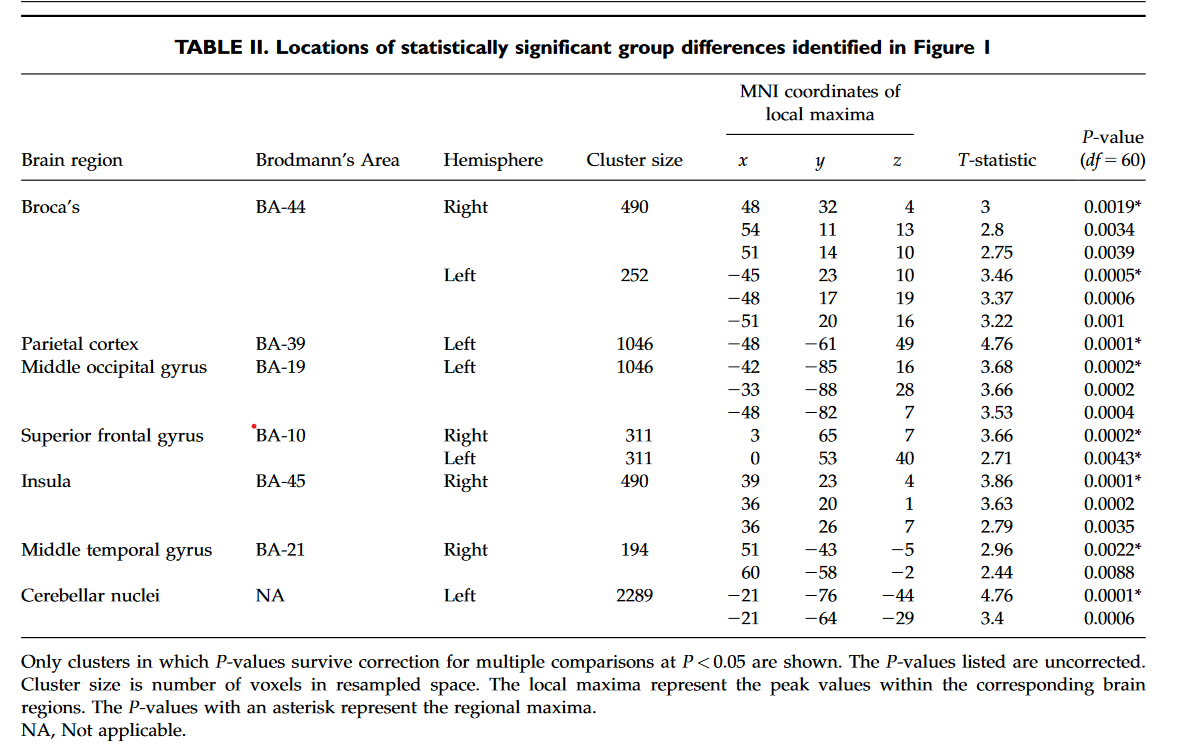

样本特征:与口吃者相比,对照组的智商全面得分略高,具有统计学意义。 组间灌注值对比:与流利的对照组相比,口吃组的Broca区 (P < 0.0043) 和额上回 (P < 0.0015) 的静息 rCBF 值较低 (P < 0.0001)(图 2)。

这项研究首次使用灌注MRI来研究口吃者的大脑活动差异。与健康对照组相比,口吃组静息状态下双侧Broca区和额上回rCBF降低,Broca区rCBF值与口吃严重程度呈负相关,并向后延伸至语言环路的其他部分;与健康对照组相比,口吃组小脑核团和顶叶皮层的rCBF增加。在儿童分析中,所有发现都没有改变。不同年龄阶段研究结果的一致性表明,Broca区rCBF降低可能代表了一种稳定的特质脆弱性,没有这种脆弱性,口吃可能不会表现出来。灌注与口吃严重程度的负相关表明,口吃越严重,Broca区和语言环路后部的rCBF降低越大。 Broca区是用于语音生成的神经网络的关键组成部分,Broca区局部脑血流量的降低会干扰运动规划、语音和句法加工以及词汇提取,导致非流利性。这种严重程度的相关性向后延伸至弓状束的邻近组织,提示当Broca区存在的组织紊乱向后延伸至弓状束时,语言环路功能恶化,产生更严重的症状。对所有参与者的rCBF与运动表现的相关性进行的事后分析支持了对主要发现的解释。使用优势手的手指敲击速度与对侧感觉和运动语言区rCBF的正相关表明,更好的运动表现伴随着语言区更大的rCBF,口吃者语言区rCBF的减少不仅代表言语行为的计划和执行,而且更普遍地代表简单的感觉运动过程。rCBF 与语言区头侧双侧感觉运动区优势手的手指敲击速度呈负相关,这表明在感觉运动皮层中需要相对较少 rCBF 以产生相当水平的运动表现的人,这种简单运动任务的速度更快因此,它们的感觉运动皮层中的神经处理效率更高。 额斜束是连接布罗卡区和额上回的深层额叶通路,额上回负责语言的启动和自发性。该束的损伤会导致言语减慢和停顿。额上回区域 rCBF 减少可能反映斜束中的组织紊乱。神经影像学和病变研究表明,小脑核团有助于言语运动控制。在口吃组中,小脑 rCBF 的增加可能代表对Broca区和相关语言回路中存在的基于运动的不流畅的补偿反应。同样,顶叶皮层 rCBF 的增加可能代表使用高阶、多感觉整合过程来补偿口吃组的不流畅,因为功能性 MRI 研究表明顶叶皮层与参与言语产生的初级感觉运动区域有广泛的联系。感觉运动语言系统以外区域的异常 rCBF 表明网络的参与超出了负责正常语音产生的关键解剖区域。